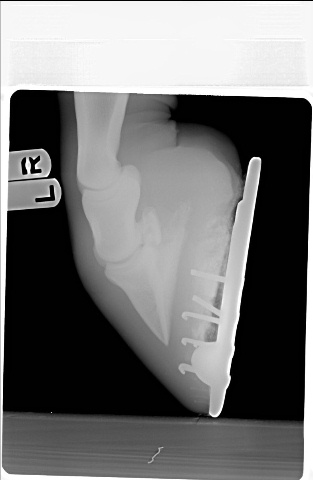

Posted on Tuesday, Apr 26, 2005 - 11:25 pm: This vet seems to feel that the farrier's work is to blame...however, he also respects my farrier and thinks I made a good choice.Here are the xrays from the farrier series.

Posted on Wednesday, Apr 27, 2005 - 7:24 pm: I was just thinking his toes looked long and I was impressed by the number of nails plus clips to hold the shoes on. If his angles are different than they normally are, or if they were changed very much in one shoeing, it could be enough to make the horse lame, at least for a while. I don't feel qualified to comment on anything else, but think you should wait for Dr. O's comments. |

Posted on Thursday, Apr 28, 2005 - 8:22 am: Concerning your vets statements no I do not think the injections were diagnostic one way or the other and agree with Sara, if at all possible I would like to see the toe squared off more.DrO |

Posted on Tuesday, Jul 19, 2005 - 9:07 pm:  What do you all think? I can't remember when this was taken...but just to give you a before and after. The vet said he has/had severely underslung heels and it was putting pressure on the DDFT - which is he says the most likely cause of my horses' problems. |

Posted on Wednesday, Jul 20, 2005 - 12:49 am: Dear Aileen,In viewing your xrays, I am wondering if the nail closest to the apex of the (I don't know the exact name) bone, in the right front is supposed to be that close to that bone. Do you know Dr.O ? The hind looks too short. The front right has a longer toe and higher heel. The left has a lower heal and a more rounded toe. It may be the photo but they look uneven to me. I have been through 3 shoers in six years. All with impeccable resumes. Go figure. There is a Farrier College/Hoof Hospital in Salinas, California. I have heard people trailer in from different states all the time just to get a horse shod correctly once. Then a good farrier can follow the balance of all 4 hooves. Brave is gorgeous. I do agree with the others, he could lose a little in the middle. Especially during this tremendous summer heat wave. All of the top trainers keep their horses quite fit. Although photos do add weight to any image.  Good Luck!! WTG |

Posted on Wednesday, Jul 20, 2005 - 7:36 am: WTG since the radiographs are 2 dimensional and we only have lateral views you cannot evaluate the nails positions with respect to the bone. For instance the nail could be tapped to the outside of the foot and would have the same appearance.Ailleen the angles, distance, and low light make evaluation difficult. Better would be to maintain the distance but to telephoto in just a bit to the point where you get distal cannon, fetlock and hook. Flash or outside with the sun behind you will improve the lighting. Also the closer the camera is to the ground, to avoid foreshortening, the better. DrO |